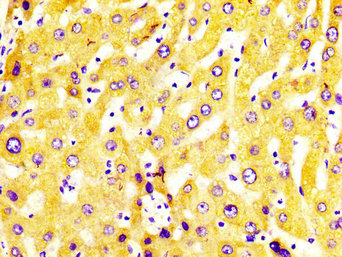

• IHC image of CSB-PA006417LA01HU diluted at 1:400 and staining in paraffin-embedded human liver tissue performed on a Leica BondTM system. After dewaxing and hydration, antigen retrieval was mediated by high pressure in a citrate buffer (pH 6.0). Section was blocked with 10% normal goat serum 30min at RT. Then primary antibody (1% BSA) was incubated at 4°C overnight. The primary is detected by a biotinylated secondary antibody and visualized using an HRP conjugated SP system.